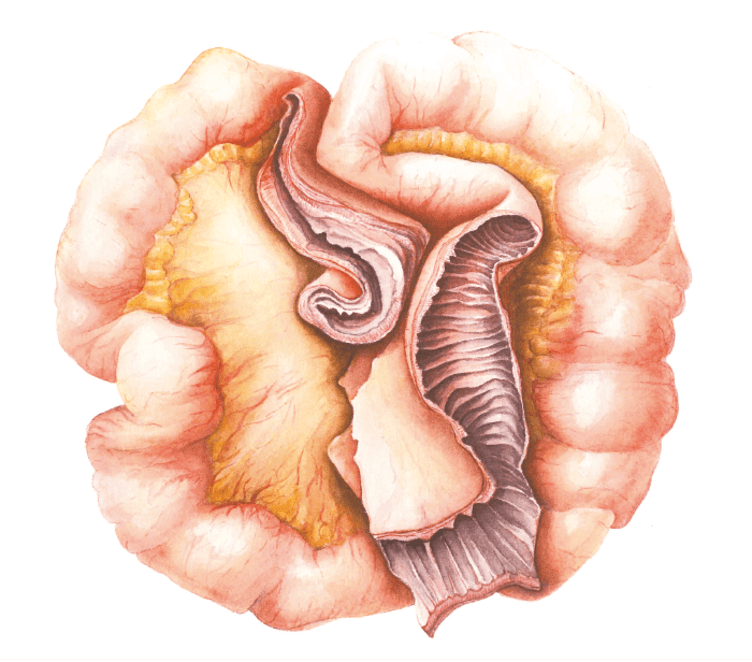

Radiation Structure of the Terminal Ileum

The wall of the ileum in this traditional watercolor illustration is grossly thickened and the lumen narrowed, with a healthy section also displayed to show the difference.

Louise Hinman, artistamedico.com